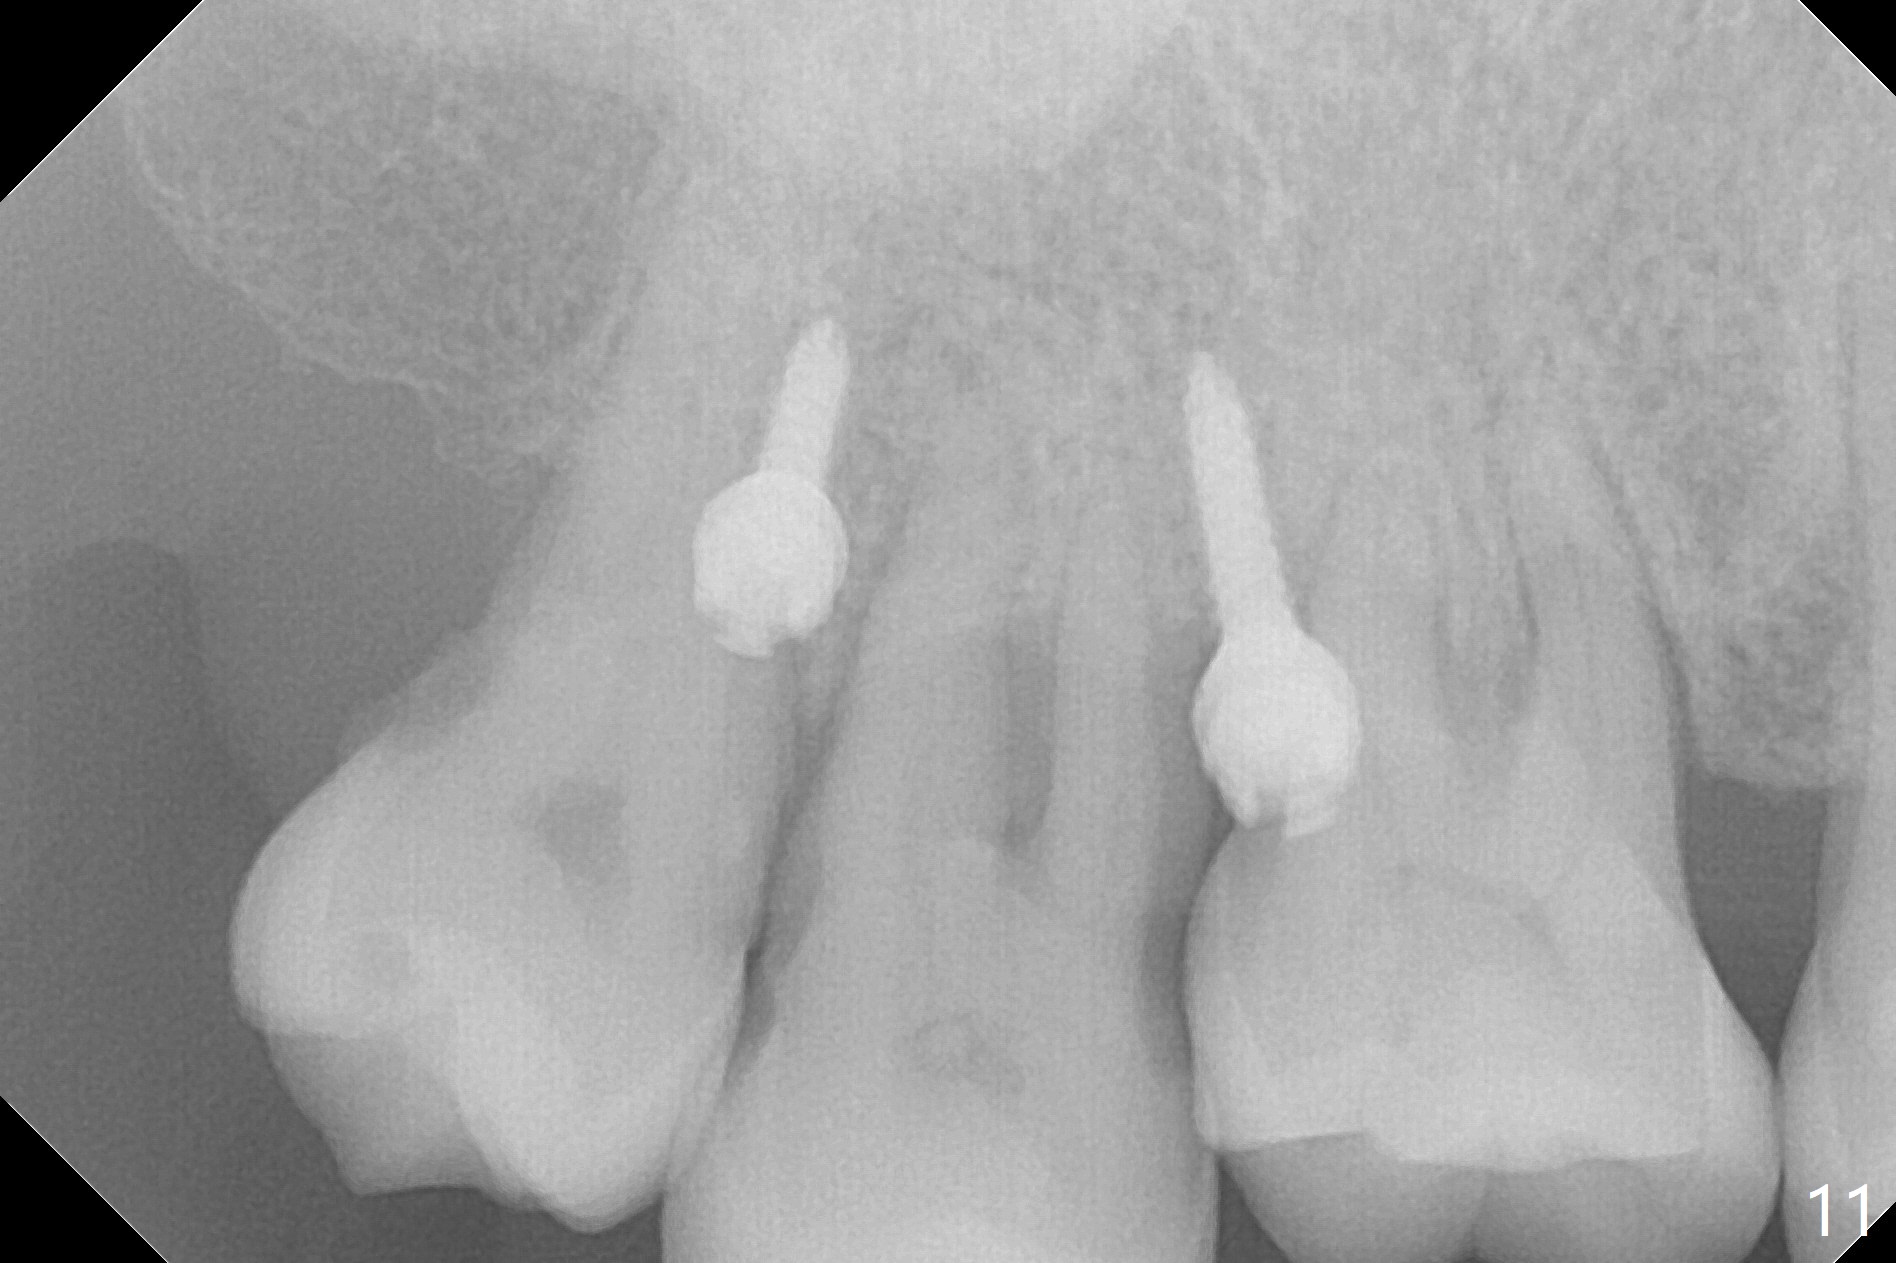

Two days post #31 implant placement, the patient returns for orthodontic intrusion of the tooth #2 with mini-implants (Fig.1). The palatal cusps have been trimmed (Fig.2 ^), since they almost contact a healing abutment at #31(*, Fig.3). Two mini-implants are to be placed mesiobuccal and distopalatal to the affected tooth. After minimal injection of Lidocaine, a 1.6x6 mm Tomas implant is placed in full length mesially (Fig.4), while the other (1.6x8 mm) half way (Fig.4). Following change in implant site mesially (Fig.6 >), the implant is half inserted (Fig.5). It appears that the tip of the distal implant is toward the tooth #1 (Fig.5). After withdrawing the implant partially, it is re-directed to apparently ideal trajectory (Fig.7). Ideally the mesial implant (Fig.8) should have been placed partially initially (Fig.4,5,7) so that the trajectory could have been able to be changed.

The buccal implant becomes loose in 2-3 months. When the wound heals (Fig.9 <), a 1.6x`10 mm implant is placed with the help of PAs for trajectory (Fig.10,11) and in the nonkeratinized gingiva (higher, the crestal bone may have been traumatized by previous implant placement, Fig.12). Two months later, the tooth #2 is partially intruded (Fig.13). A provisional (Fig.14 P) is fabricated in the osteointegrated implant at #31 with supraocclusion so that the remaining dentition has no occlusal contact (*). The periodontally compromised tooth #2 becomes in buccoversion in 2 months. The provisional is removed, while a lingual button is placed in the buccal surface of the tooth #2 (Fig.15). With power chain attached to the lingual mini-implant, the tooth #2 is lingualized in 2 months. The provisional and the implants are reused for final intrusion (Fig.16). The treatment is nearly 11 months. The buccal implant, although placed in the movable mucosa, remains stable and healthy (Fig.17). The tooth #1, as a guiding plane (to prevent #2 from distalization during intrusion), is not extracted after intrusion is completed.